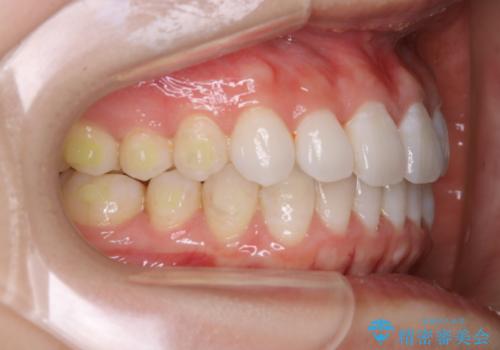

- インビザライン(マウスピース矯正)の治療中にステインが気になり、クリーニング希望とのことでした。

アタッチメントの周囲などに、ステインの付着や、プラークがみられたためPMTC(自費クリーニング)30分コースを行いました。

インビザラインで矯正治療中に、クリーニングを行ったbeforeafter写真です。